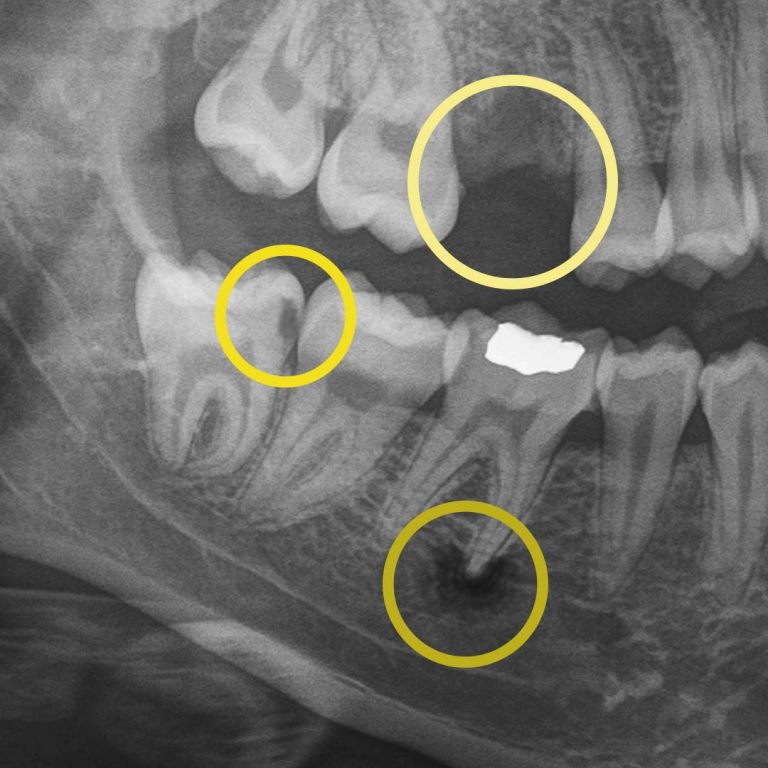

Digital X-rays allow us to see what the human eye simply can’t. They can detect hard and soft tissue changes, and if your dentist uses AI-technology, it can detect changes up to 10x quicker than traditional digital X-rays. More importantly, they help us personalize your care, track your oral health over time, and show you exactly what’s happening, so surprises are limited.

Digital X-rays allow us to look beyond what’s visible. They help us detect:

• cavities between teeth.

• early decay hiding under fillings or crowns.

• bone changes related to gum disease.

• infections at the root of a tooth.

• subtle cracks.

For example, during a routine digital X-ray, we may notice a small shadow between two teeth. To the naked eye, everything can look healthy, but that faint shadow often tells us the enamel in that area is starting to weaken. This is considered early-stage tooth decay, sometimes called early “caries.”

At your next X-ray visit, we’ll compare images to see whether that spot has stabilized or improved. If the area worsens and the enamel breaks down further, a small dental filling may be necessary to prevent deeper decay damaging the tooth structure. If the decay continues unchecked and reaches the inner portion of the tooth where the nerve lives, treatment becomes more complex, often requiring root canal therapy, which can be time-consuming, uncomfortable, and costly.